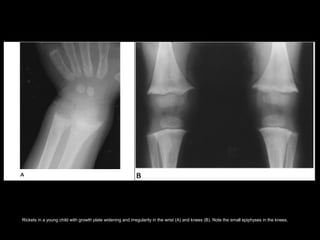

• The regions of highest yield on

radiologic evaluation of rickets are those

that are undergoing rapid growth.

– Costochondral junctions of middle ribs

(rachitic rosary)

– Distal femur

– Both ends of the tibia

– Distal radius and ulna

– Proximal humerus.

Rickets in a young child with growth plate widening and irregularity in the wrist (A) and knees (B). Note the small epiphyses in the knees.